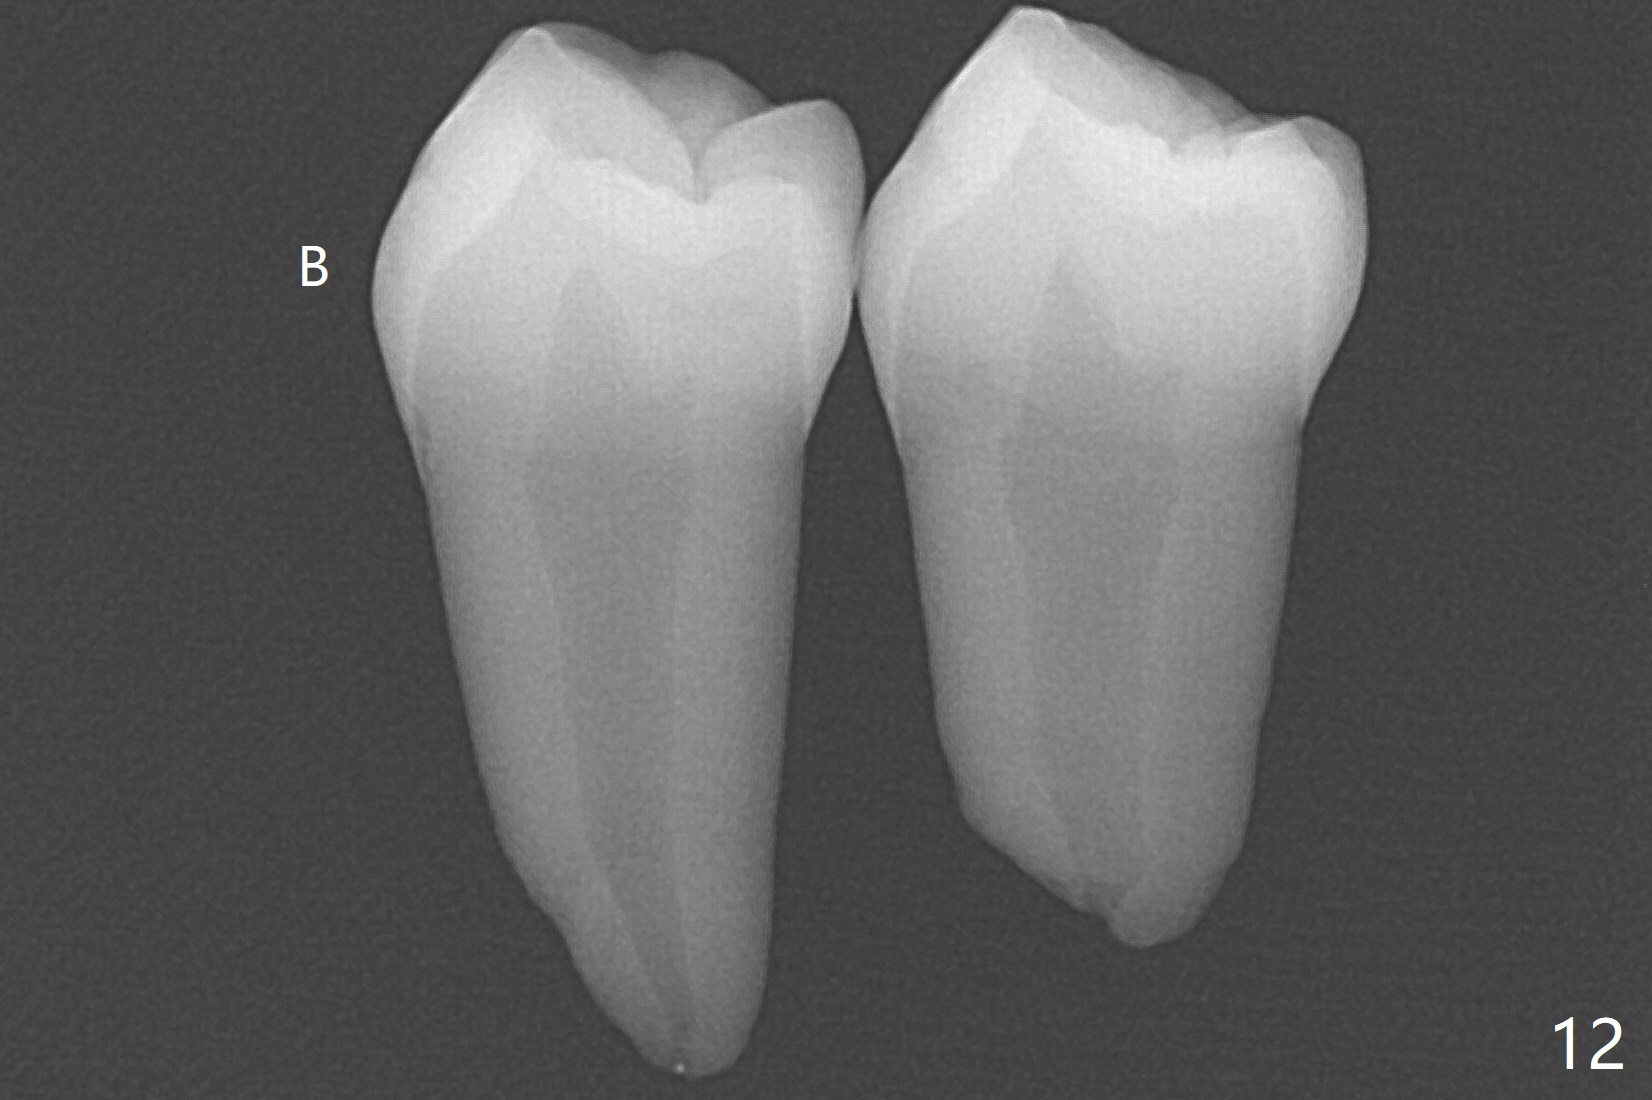

A 14-year-old woman with crowding returns to clinic for extraction of the 1st bicuspids. Orthodontic treatment has started partially. Because of severe caries at UR5 (Fig.1 *), BWs and PA are taken, which reveal DO incipient caries at UL, LL5 (Fig.2) and large PARL at UR5 (Fig.3 *). Upon receiving a revised treatment plan, four of 2nd bicuspids are extracted. The large PARL is confirmed intraop. Examination of the extracted teeth shows mesial caries at UL5, which is not detected by X-ray (Fig.4 <). By comparison, DL caries of UL5 is more severe (Fig.5). Check the neighboring teeth for caries when the patient returns for recall. The pulpal exposure of UR5 is large (Fig.6). So is the pulpal chamber (Fig.7). The large canal (Fig.7) in fact consists of 2 ones (Fig.11 red arrows) with a separation in between (*). The DL caries at LL5 is at the stage of decalcification (Fig.8), not visible in X-ray (Fig.12, as compared to Fig.7 >).